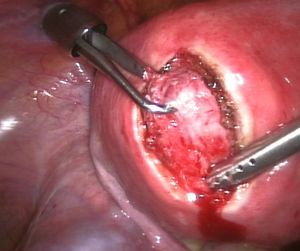

Myomectomy

Myomectomy is a surgery to remove one or more fibroids. It is usually recommended when more conservative treatment options fail for women who want fertility preserving surgery or who want to retain the uterus.[60]

- In a hysteroscopic myomectomy (also called transcervical resection), the fibroid can be removed by either the use of a resectoscope, an endoscopic instrument inserted through the vagina and cervix that can use high-frequency electrical energy to cut tissue, or a similar device.

- A laparoscopic myomectomy is done through a small incision near the navel. The physician uses a laparoscope and surgical instruments to remove the fibroids. Studies have suggested that laparoscopic myomectomy leads to lower morbidity rates and faster recovery than does laparotomic myomectomy.[61]